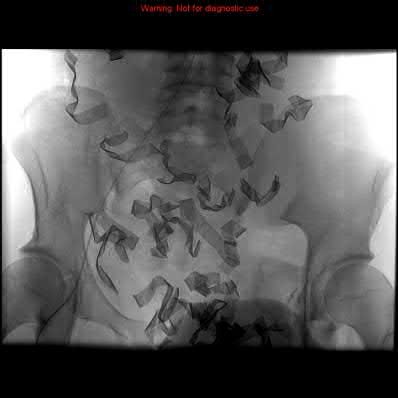

A 23-year-old female is an unrestrained driver in a motor vehicle collision, sustaining the injury shown in Figure A. She subsequently undergoes reduction and percutaneous bilateral iliosacral screw placement. Which of the following is the most likely neurologic complication associated with percutaneous iliosacral screw insertion?

Figure A shows an unstable bilateral pelvic ring injury. Percutaneous posterior iliosacral screw fixation places the L5 nerve root at risk as it courses across the sacral ala. Injury to the L5 nerve root would typically result in weakness in great toe extension and sensory changes on the dorsum of the foot. It is important to notice that L5 often partially innervates tibialis anterior along with L4, so weakness to ankle dorsiflexion may be present as well. Illustration A shows the post-operative films with bilateral iliosacral screws.

Routt et al examined the sacral slope and sacral alar anatomy in cadavers and a series of consecutive patients. They determined that the pelvic outlet and lateral sacral plain films provide the best plain radiographic views of the sacral ala. They recommended routine usage of these views intraoperatively to guide screw placement.

In another study, Routt et al reported on the early complications of percutaneous placement of iliosacral screws for treatment of posterior pelvic ring disruptions. While technically challenging, this technique leads to less blood loss and lower rates of infection compared to traditional open techniques.

Illustration B displays the root diagrams for sensation, reflex, and motor of the L4-S1 nerves.